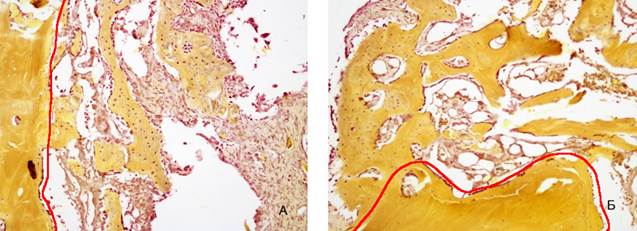

На 14-е сутки в области дефекта вокруг имплантата выявлены сформированные костные трабекулы, клетки остеобластического ряда и малочисленные остеокласты. В сравнении с предыдущим сроком наблюдения имеется тенденция к увеличению площади и толщины трабекул формирующейся костной ткани, возрастает численность упорядоченно расположенных коллагеновых волокон. При сравнении показателей, характеризующих процесс остеогенеза в 1 и 2 группах животных, отмечено статически значимое увеличение площади формирующейся костной ткани (р=0,04), толщины трабекул (p=0,007) и количества волокон в группе животных с использованием ОТП (таблица 2, 3, 4, рисунок 6).

Рис. 6. Зона регенерации на 14 сутки эксперимента: выявлена большая толщина и площадь формирующихся костных трабекул при использовании ОТП. Красным маркером показана граница между формирующейся костной тканью и зрелой костью: А) 2 группа, Б) 1 группа. Окраска по Шморлю. Увеличение *40

Примечание: фотография выполнена авторами в ходе эксперимента.

Параллельно с увеличением толщины трабекул выявлено статистически значимое увеличение площади трабекул и площади формирующейся костной ткани (таблица 3). При сравнении результатов выявлены достоверные различия на всех сроках эксперимента. На рисунке видно, что уже на 14 сутки более развитые трабекулы и в большем количестве выявляются в препаратах с ОТП (рисунок 6).